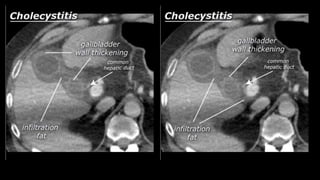

• Cholecystitis

• A complication of bile stones is an infected

gallbladder or cholecystitis. Cholecystitis

rarely occurs in the absence of bile stones.

Ultrasound is also best suited to diagnose

cholecystitis. Ultrasound improves the

visibility of the bile stones, and gallbladder

compressibility can be evaluated (dynamic

examination). Absent compressibility

constitutes a key characteristic of

cholecystitis (see abdominal ultrasound

class). Other characteristics of cholecystitis

on CT include gallbladder wall thickening

and infiltration of the fat surrounding the

gallbladder. A common complication of

cholecystitis is gallbladder perforation,

where bile leaks into the abdominal cavity

(biloma).

• Cholecystitis • Acomplication of bile stones is an infected gallbladder or cholecystitis. Cholecystitis rarely occurs in the absence of bile stones. Ultrasound is also best suited to diagnose cholecystitis. Ultrasound improves the visibility of the bile stones, and gallbladder compressibility can be evaluated (dynamic examination). Absent compressibility constitutes a key characteristic of cholecystitis (see abdominal ultrasound class). Other characteristics of cholecystitis on CT include gallbladder wall thickening and infiltration of the fat surrounding the gallbladder. A common complication of cholecystitis is gallbladder perforation, where bile leaks into the abdominal cavity (biloma).